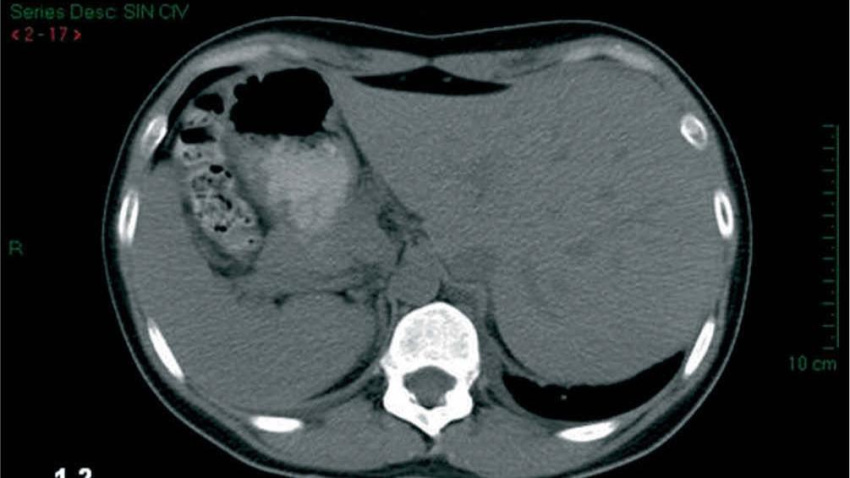

Imagen de la cavidad abdominal de un paciente con esta extraña anomalía

Tomografía computarizada de un paciente con esta anomalía

Esta condición se llama situs inversus totalis, "una rara condición congénita en la que los órganos principales del cuerpo están invertidos o espejados respecto a su posición normal". Agrega que esta enfermedad, como tal, no supone un riesgo para la salud de la persona ni tampoco conduce, precisamente, a problemas de salud.

"El hígado en la izquierda y el bazo en la derecha", ejemplifica.